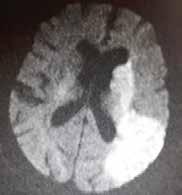

Rzadko stosowaną w codziennej praktyce klinicznej jest technika obrazowania czynnościowego (functional MRI – fMRI). Polega ona na detekcji zwiększenia utlenowania ośrodków w korze mózgu po zadziałaniu odpowiednich bodźców, np. wzrokowych, słuchowych czy ruchowych. Badanie ocenia zaburzenia czynności kory mózgowej, co niekiedy istotne jest w diagnostyce przedoperacyjnej guzów mózgu. Niekiedy w praktyce klinicznej w różnicowaniu uwidocznionych niejasnych co do charakteru zmian ogniskowych stosuje się spektroskopię rezonansu magnetycznego (magnetic resonance spectroscopy – MRS). Technika oparta jest na dyskretnych różnicach sygnału RM różnych związków chemicznych w tkance nerwowej, dzięki czemu uzyskuje się widma spektroskopowe określające stężenie podstawowych metabolitów. Najczęściej stosowana jest spektroskopia protonowa. Najistotniejszymi metabolitami w spektroskopii protonowej są: N-acetyloasparaginian, cholina, mleczany, kreatyna i mioinozytol. Stężenie metabolitów wraz z ich wzajemnym stosunkiem ulega zmianie w różnych patologiach, zwłaszcza w guzach. Na rycinie 1.35 przedstawiono nadostrą fazę udaru niedokrwiennego.

Rycina 1.35. Nadostra faza udaru niedokrwiennego. Badanie RM w sekwencji DWI uwidacznia restrykcję dyfuzji w lewej półkuli mózgu w zakresie unaczynienia gałęzi tętnicy środkowej mózgu lewej.